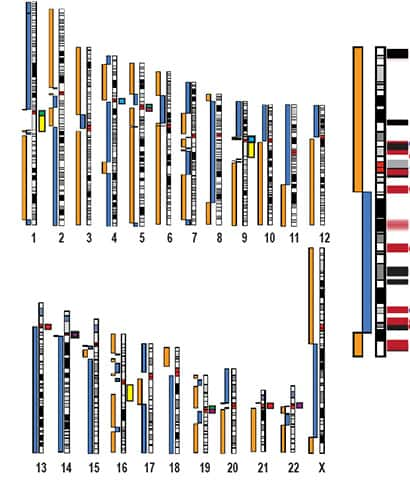

Après le chromosome X, l'équipe s'est attelée au séquençage des autres chromosomes. Mais cela risque de s'avérer un peu plus compliqué, notamment concernant les chromosomes acrocentriques (13, 14, 15, 21 et 22), qui ont un centromèrecentromère très grand et donc beaucoup plus de répétitions.

Quatre ans après le premier décodage des 24 chromosomes qui composent le génome humain, l'affinement se poursuit dans les laboratoires du monde entier afin de compléter les pans lacunaires. C'est dans la revue Nature qu'a été publiée la séquence complète du chromosome 5 qui marque le parcours de la moitié du chemin de la démarche d'approfondissement entreprise, soit encore douze chromosomes à analyser dans le détail.

En collaboration avec le Centre du Génome Humain de Stanford (SHGC), les chercheurs du département de l'ÉnergieÉnergie de Californie (Joint Genome Institute), sont venus à bout du chromosome 5, le douzième à se révéler entièrement. De même que pour les chromosomes qui l'ont précédé, une carte d'identité a pu être établie pour le n° 5.

Ce dernier ne présente pas moins de 180,9 millions de paires de bases pour 923 gènes, dont 66 sont connus pour être impliqués dans diverses pathologiespathologies, sans pour autant que l'on connaisse les mécanismes mis en jeu. Selon Spencer Abraham, secrétaire à l'Énergie américain, la connaissance de « cette séquence extrêmement précise sera à n'en pas douter un puissant outil dans la compréhension qu'ont les scientifiques des maladies affectant les êtres humains ». Sans savoir à quels gènes mutés les pathologies correspondent, la certitude est acquise que certains maux trouvent leur origine dans des altérations de gènes portés par le chromosome 5 : c'est le cas d'une certaine forme d'asthmeasthme, de la maladie de Crohnmaladie de Crohn (une maladie du tube digestiftube digestif qui peut entraîner un cancercancer), du syndrome de Sotossyndrome de Sotos (un désordre mental) et de l'amyotrophieamyotrophie spinale notamment.

Si les sections codantes présentent un intérêt majeur, en particulier pour la médecine, celles qui ne codent pas ne sont pas pour autant en reste. En effet la comparaison de ces régions avec des portions génomiquesgénomiques d'autres espècesespèces animales permet l'établissement de thèses nouvelles ou la confirmation d'anciennes, dans le domaine de l'évolution. Ainsi, une séquence présente sur le chromosome 5 se retrouve en tous points identique chez le chimpanzéchimpanzé, à ceci près qu'elle y figure inversée. Une modification de ce genre pourrait être à l'origine de la différenciation entre l'homme et le singe.

Même si la moitié des chromosomes restent à analyser complètement, l'on estime le décodage quantitativement proche des 100 % à l'heure actuelle. Mais le chromosome 5 nous le prouve, en génétiquegénétique, le détail a son mot à dire, le tout est de le décrypter.